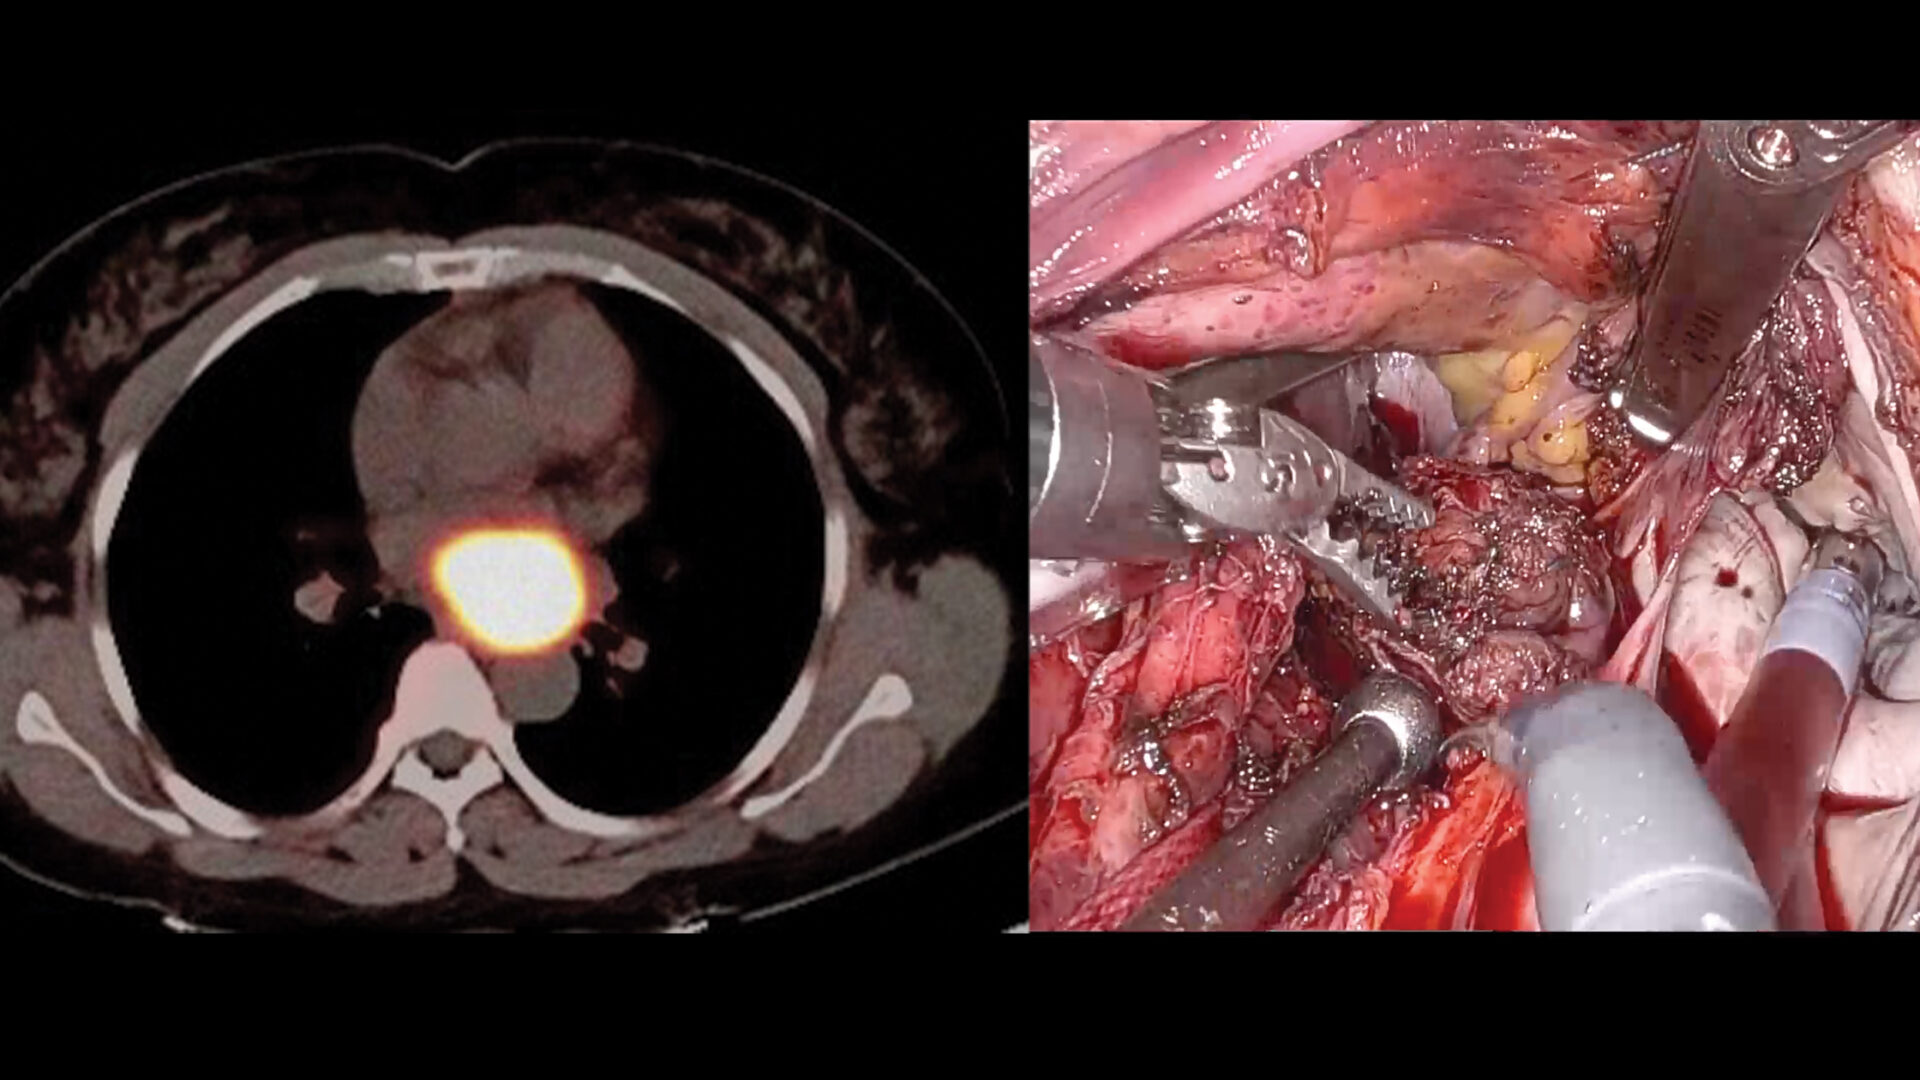

The NYU Langone surgical team performing the fully endoscopic robotic resection of a retrocardiac paraganglioma. Source: NYU Langone Health.

The operation involved placement of five side ports through the right chest wall. Following dissection between the back of the heart and the spine, a 5-cm tumor was identified attached to the roof of the left atrium and extracted.

Due to thinning or tearing of the left atrial roof, the atrial wall was replaced with a bovine pericardial patch sewn between the right and left pulmonary veins. A sample of the mass was sent to pathology for review.